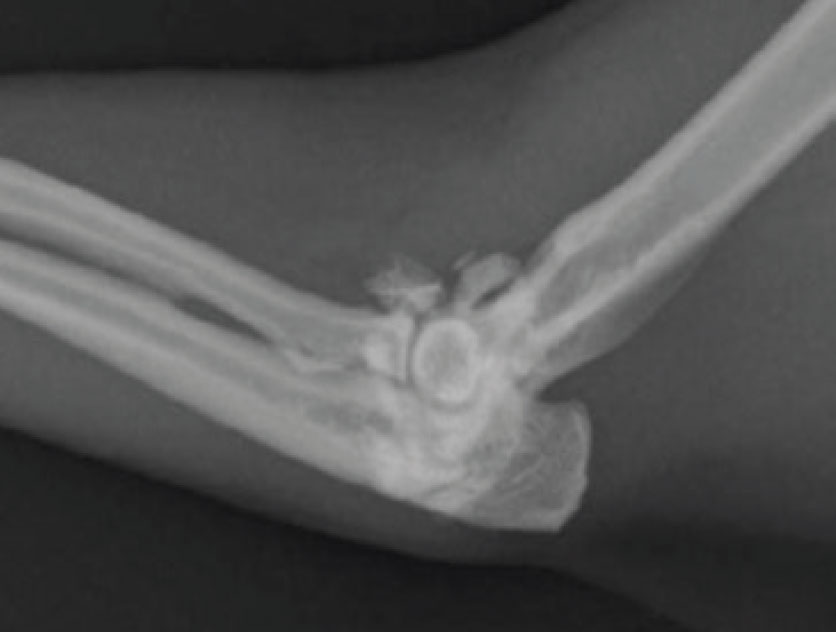

Degenerative joint disease refers to damage in both the appendicular and axial skeletal systems, with most of the cases diagnosed as osteoarthritis. OA implies a joint problem, primarily associated with degeneration and loss of cartilage and proliferation of bone in the form of osteophytes around the joint. This results in a joint that has a reduced range of motion and one that is undergoing low grade inflammation resulting in varying degrees of pain and swelling of the offending joint(s). It is common in cats where multiple joints are impacted. In cats, OA usually occurs as a primary problem with no easily identifiable underlying cause, but it can also occur secondary to underlying developmental joint disease such as hip dysplasia (see Figure 2) or subsequent to a joint injury such as an intra-articular fracture or luxation. Cats develop osteoarthritis in all their large joints, but particularly the hip, hock and elbow joint3,4 (see Figure 3). Over 80% of cats older than 12 years of age had axial skeletal changes.4 Appendicular skeletal changes are even more common with over 90% of cats of all ages having radiographic changes in at least one joint.3

Figure 3: Elbow osteoarthritis in an 11-year-old Burmese cat. There are peri articular osteophytes and joint mice. Bilateral elbow changes were present.